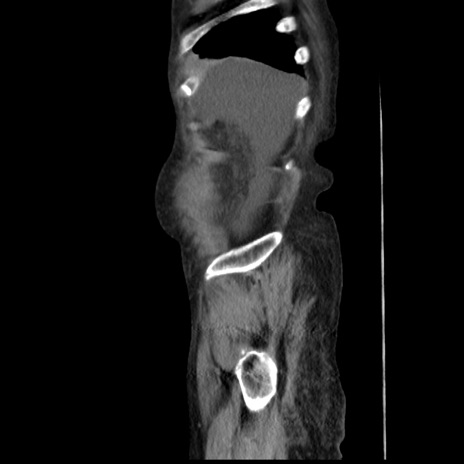

症例31(矢状断像)

【症例】80歳代 女性

【主訴】腹部膨満感

【現病歴】他院にて肝硬変にてフォロー中。1週間前から便秘、腹部膨満感、臍部腫瘤あり受診となる。

【既往歴】肝硬変

【身体所見】腹部膨隆あり、皮膚変化なし、疼痛なし。

【データ】WBC 4600、CRP 0.25